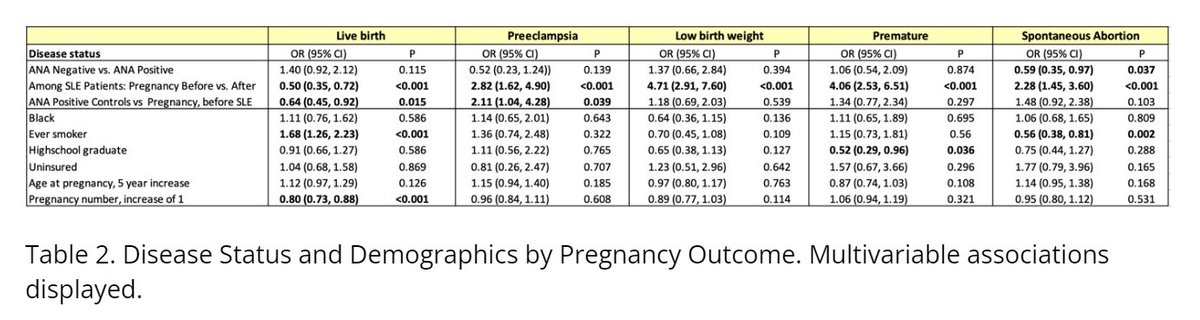

Study on pregnancy outcome disparities in SLE:

- Analyzed 685 women, 1888 pregnancies

- Pre-SLE state linked to fewer live births, higher preeclampsia risk

- Outcomes worse post-SLE diagnosis

#ACR24 abst#0440 @RheumNow https://t.co/NpEYQZ73uo

Bella Mehta bella_mehta ( View Tweet)